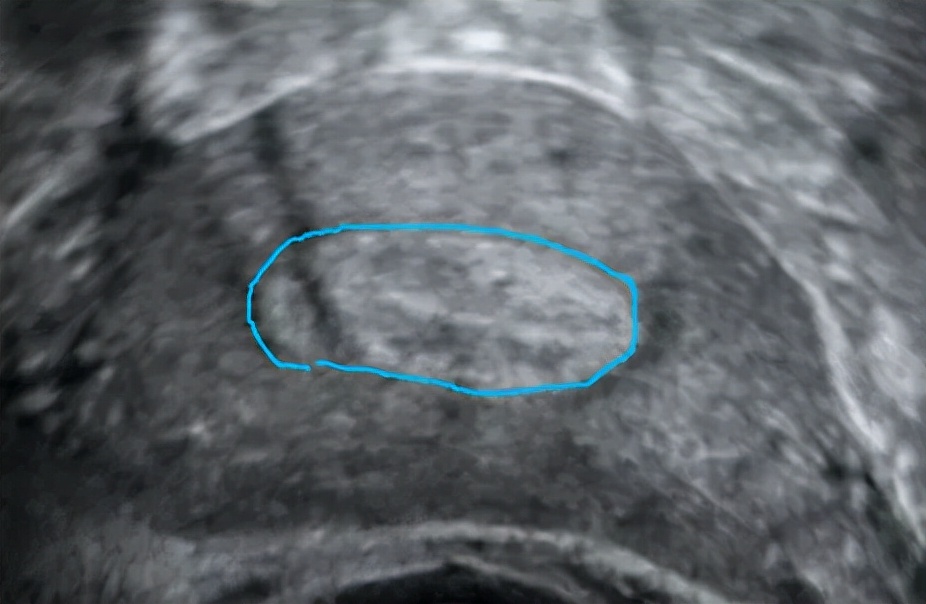

正常内膜长这样

画蓝线的地方是正常内膜的范围

内膜本该连续的地方却见到一处连续性中断的地方

箭头所指就是粘连处

这都是在内膜有一定厚度和形态且粘连程度较明显的情况下,超声可以看到的间接征象。现在不止二维的超声可以检查宫腔粘连,三维超声也可筛查出宫腔粘连。